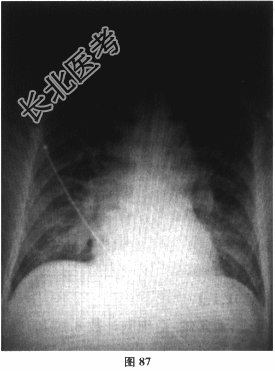

- 多项选择题2.[提示]实验室检查:血常规: 白细胞计数8.07×109/L,中性粒细胞百分比78.6%, 血红蛋白浓度150g/L,血小板计数174×109/L; 生化:肝肾功能正常, BNP246pg/ml,心肌酶谱: CK、CK-MB、cTNI值均在正常范围,hsCRP51.82mg/L, D二聚体0.36mg/L;胸片(图87): 心影增大,双肺纹理增多紊乱, 肺野内可见片状模糊影,内带为著, 双肺门增大,考虑肺水肿; 血气分析:pH7.39, PaCO243mmHg,PaO262mmHg, SaO292%;ECG如图88所示。